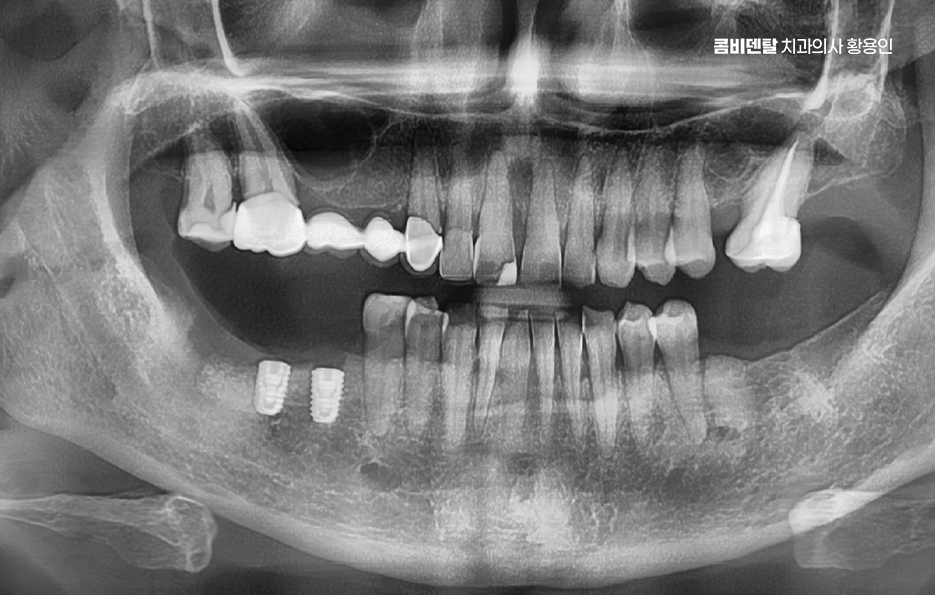

임플란트 치료의 주된 원리는 '골유착'에 있는데 이 단어가 조금 생소할 수 있지만 쉽게 말하면 임플란트의 인공치근, 자연치의 뿌리 역할을 대신하는 인공치근은 티타늄 재질로 구성되어 있고 잇몸뼈 안에 심으며 그 뼈가 이 인공치근을 자기 뼈처럼 감싸서 단단하게 붙는 현상을 말하는 거예요

티타늄은 인체에 생물학적으로 안정적인 금속이라서 뼈가 이물질로 인식하지 않고 잘 달라붙는 성질이 있는 것으로 치조골 안에 이 티타늄으로 구성된 인공치근이 수개월 동안 안정적으로 뼈와 결합되는 과정을 거치게 되면서 자연치아에 버금가는 저작력을 갖추게 되는 것이 주된 치료 원리라고 할 수 있었어요

임플란트의 장점 이 골유착이 완성된 이후에는 그 위에 기둥을 세우고, 마지막으로 보철물을 씌우게 되는데 이렇게 되면 겉에서 보기엔 자연치아와 거의 차이가 없으며 심지어 기능적으로도 자연치아와 유사한 수준의 저작력이 가능해지며 다시 말해 뿌리부터 머리까지 인공치아를 만드는 건데 ‘뼈에 심는’ 것이기 때문에 더 안정적이고 오래 쓸 수 있는 치료인 거예요.